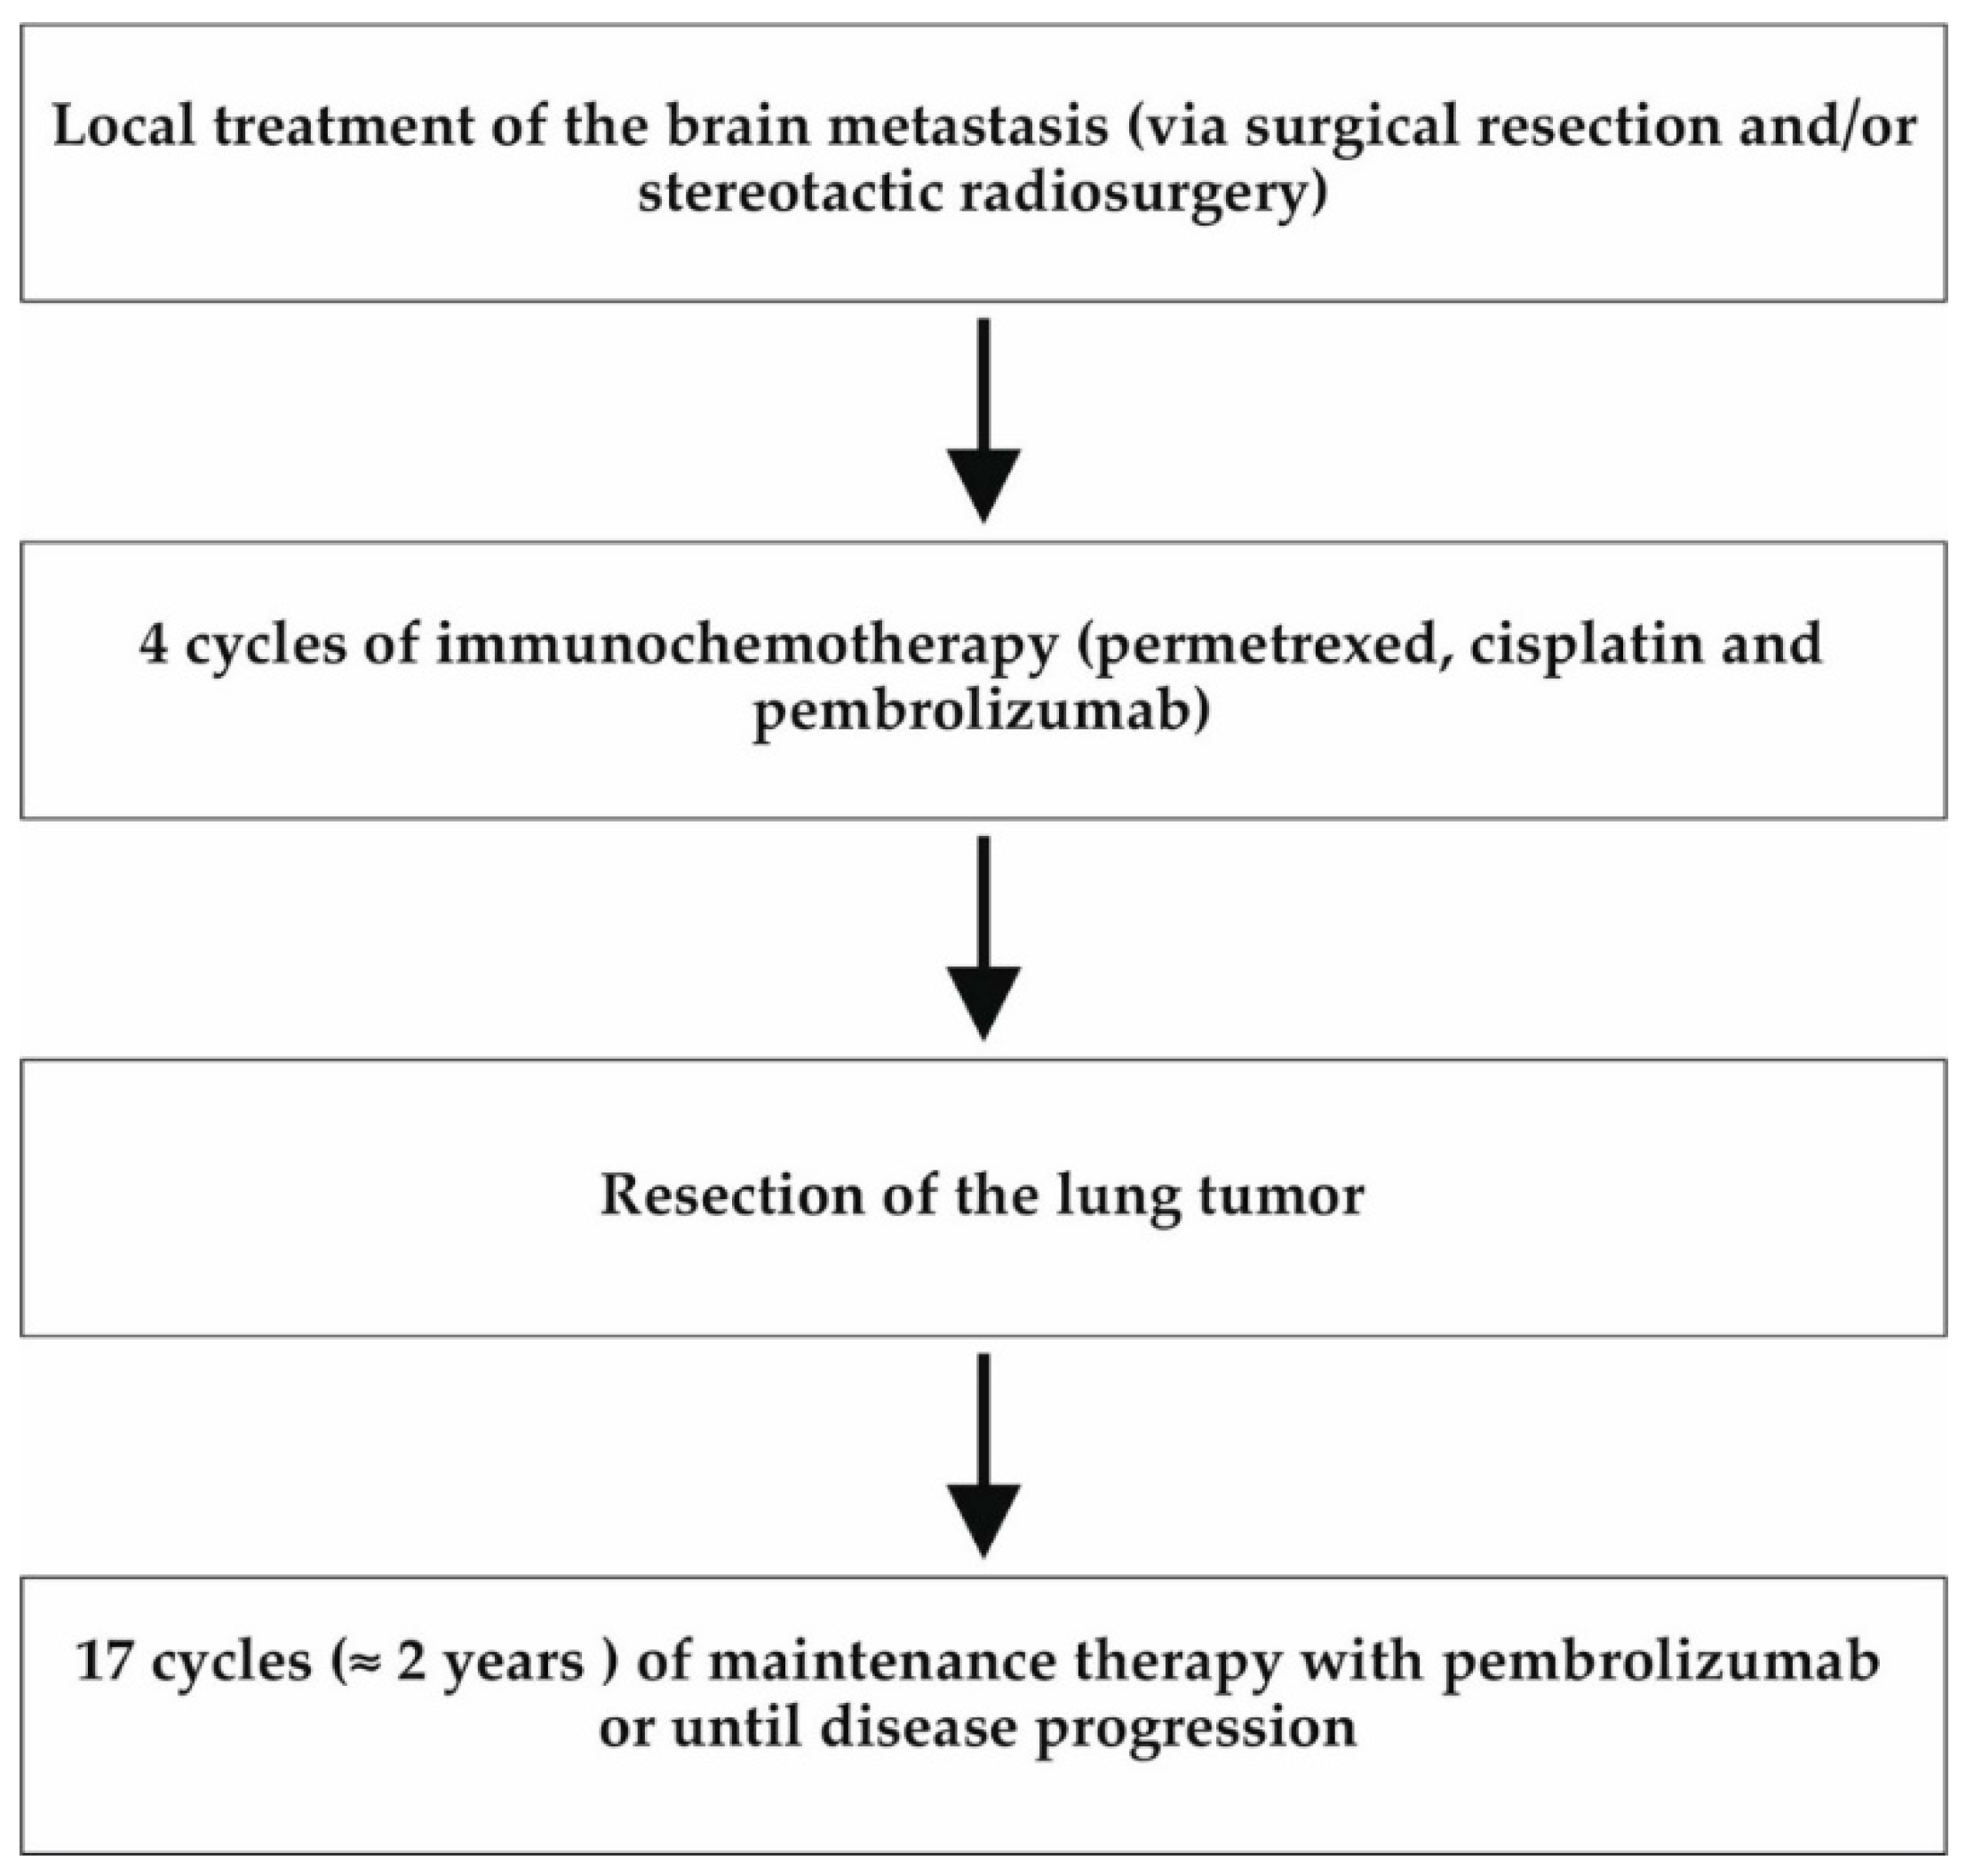

2. Materials and Methods

3. Results

3.1. Case 1